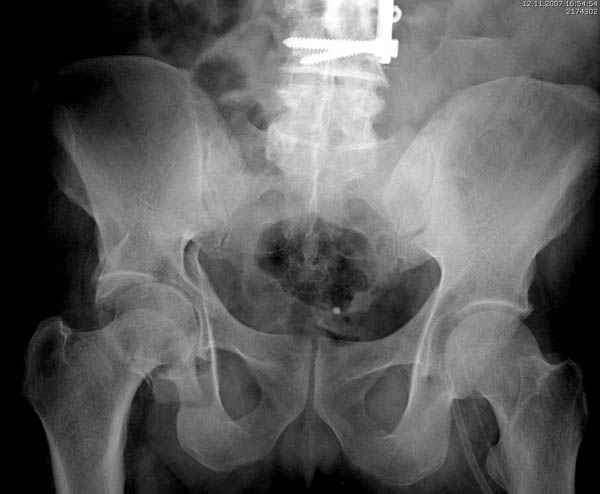

Вложение не в текстовом формате было извлечено…

Имя     : 3 Proximal hum+acetabulum Judet.jpg

Тип     : image/jpeg

Размер  : 28264 байтов

Описание: отсутствует

Url     : http://weborto.net:8080/pipermail/ortho/attachments/20071130/37ea88e5/attachment-0010.jpg